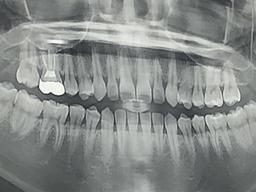

치료는 다른 치료와 달리 보험 적용 제외 대상이라 경제적 약자를 힘들게 하였습니다. 또한

치과

치료에 대한 상식이 없는 환자는 당연히 의사의 처방대로 치료를 받아야 했기 때문에 과잉치료로 인한 피해도 많았었습니다. 충치 하나 치료를 받는 데에 7만원에서 20만원까지도 비용이 청구됩니다...